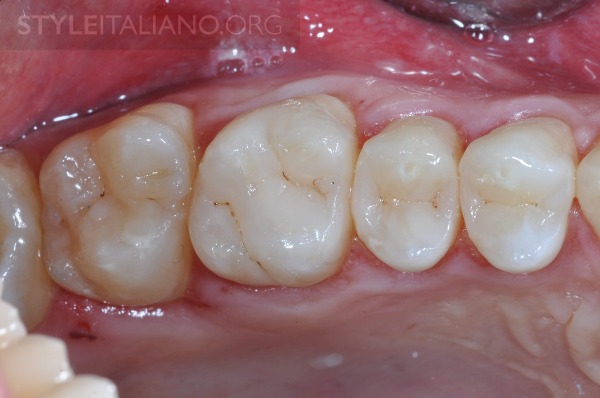

图12 拆除橡皮障后的解剖结构细节

图13 拆除橡皮障后的解剖结构细节